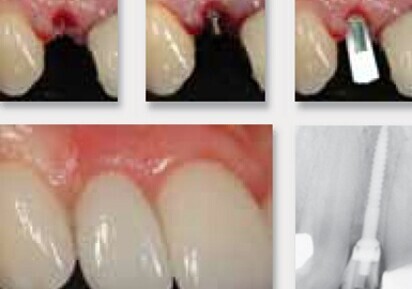

To provide more treatment options to patients without enough space for larger implants, Dentatus USA Ltd. has created a unique narrow body implant called ANEW. The titanium alloy narrow-body implants are specifically designed to fit where others can’t while being strong and safe for long-term use. The ANEW system is available in 1.8, 2.2 and 2.4mm diameters. ANEW is the only narrow-body implant with a screw-retained prosthetic system and with over 10 years of clinical research to support the safe, reliable, long-term use for single tooth replacement.

The advantages of the ANEW narrow body implants are several. First and foremost, the ANEW implants expand the patient population that are eligible for this treatment. Narrow body implants make it much easier to maintain adequate buccal-lingual bone dimensions and proper implant spacing without the need for ridge augmentation. The narrow body allows a thicker buccal bone because less bone is consumed for the osteotomy. Finally, the implants are designed to allow immediate loading.

The screw-retained prosthesis provides more flexibility for long-term maintenance. The restoration is retrievable and allows for repair or recoloring of the crown without causing micromovement that occurs with tapping off of cement retained crowns. The ANEW tapered one-piece implant design eliminates the microgap which is related to crestal bone loss, facilitates one stage surgery, provides immediate restoration and is more conducive to a flapless implant placement. Additionally, utilizing a minimally invasive flapless procedure with an immediate restoration eliminates many postoperative challenges as well as reduces total treatment time.

ANEW Implants were introduced by Dentatus in 2001, in conjunction with research by the NYU Department of Implant Dentistry, developing a specific protocol to help patients with limited inter-dental spaces. In 2004, the FDA approved ANEW Implants for long-term use.